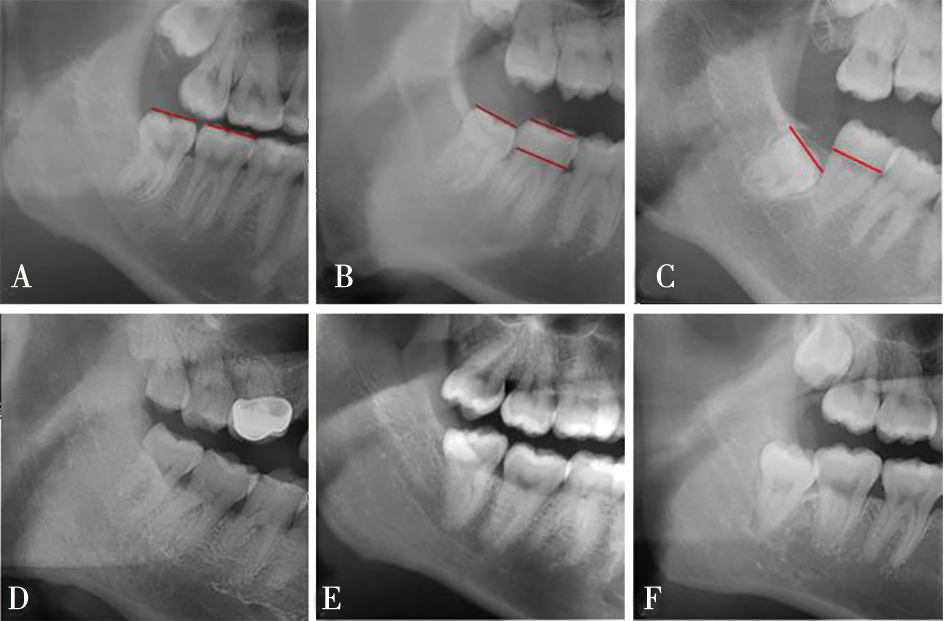

| Winter分类(曲面断层片) | 近中 | 484 | (50.26%) | 479 | (49.74%) | <0.000 1* | |

| 水平 | 566 | (52.85%) | 505 | (47.15%) | |||

| 垂直 | 1 046 | (77.20%) | 309 | (22.80%) | |||

| Pell-Gregory分类(基于第二磨牙咬合平面,曲面断层片) | 高位 | 1 115 | (81.15%) | 259 | (18.85%) | <0.000 1* | |

| 中位 | 786 | (51.37%) | 744 | (48.63%) | |||

| 低位 | 195 | (40.21%) | 290 | (59.79%) | |||

| Pell-Gregory分类(基于下颌升支,曲面断层片) | Ⅰ类 | 762 | (84.57%) | 139 | (15.43%) | <0.000 1* | |

| Ⅱ类 | 888 | (63.66%) | 507 | (36.34%) | |||

| Ⅲ类 | 446 | (40.81%) | 647 | (59.19%) | |||